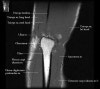

- Sagittal section

1) Biceps Brachii tendon and Brachiallis muscles

2) Radial head for radiographically occult fractures

3) Distal Triceps tendon

4. MR Arthrography : Useful for evaluation of the collateral ligaments and cartilage surfaces.

5. Elbow Arthrography : UCL pathology in throwers, Osteochondral lesions and repair, Loose bodies